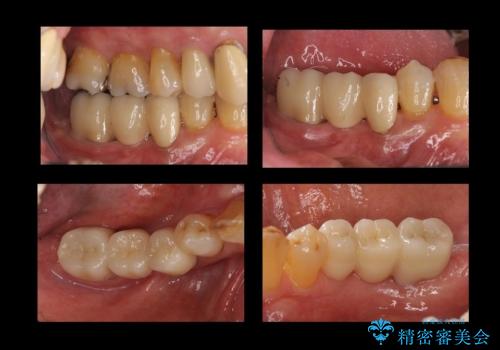

臼歯部メタルフリー再補綴